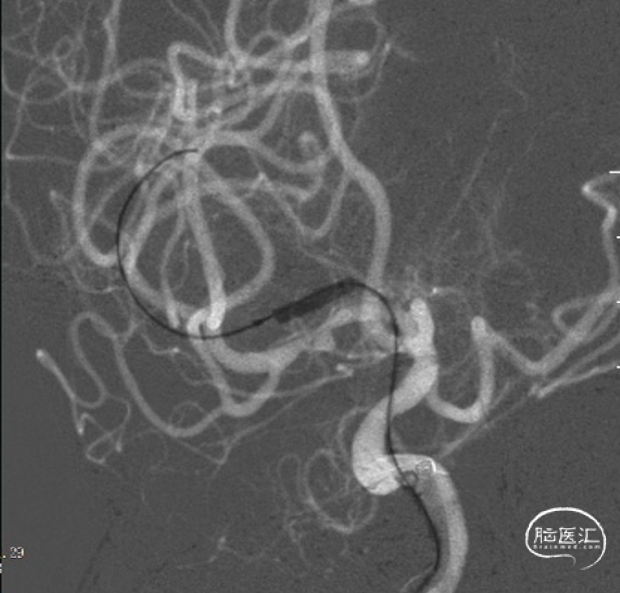

全麻下,通过同轴技术泥鳅导丝、5F VTK将6F长鞘置于右侧颈总动脉,撤出微导丝及VTK,随后路图下泥鳅导丝携6F Tethys®中间导引导管置于右侧颈内动脉C4段。撤出泥鳅导丝,在6F Tethys®中间导引导管路图下,顺导丝(交换导丝)将加奇SacSpeed® 1.75×12mm球囊置于狭窄段,路图下精确定位,以1atm/30s速度缓慢扩张球囊至6atm左右,释放球囊压力。造影提示右侧大脑中动脉狭窄明显改善,瘤样突起减少,撤出球囊。

治疗之前3D和工作位(测量病变处近远端血管管径,M1近端1.9mm,M1远端1.7mm)。